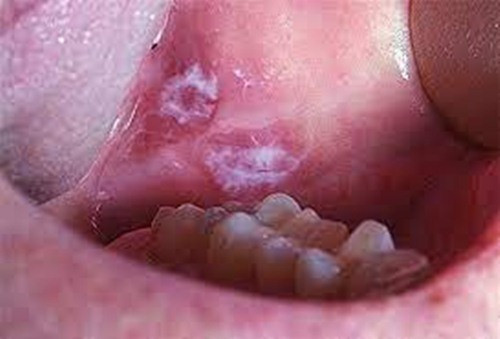

Sưng không rõ nguyên nhân, vón cục, bong tróc và thay đổi màu sắc của màng nhầy xuất hiện trong khoang miệng: Ví dụ như bạch sản, ban đỏ, liken phẳng hoặc đốm dạng lưới,… cũng cần phải cảnh giác.

Niêm mạc miệng khỏe mạnh thường có màu hồng, kết cấu tương đối đồng đều. Chúng ta có thể soi gương. Nếu mắc bệnh răng miệng sẽ xuất hiện bạch sản, ban đỏ và các tổn thương khác. Mảng màu này lúc đầu có thể phẳng, nhưng chúng ngày càng lớn hơn và xuất hiện hiện tượng chai cứng hoặc hình hạt sần sùi. Nếu điều này xảy ra, rất có thể là một tổn thương tiền ung thư sớm.